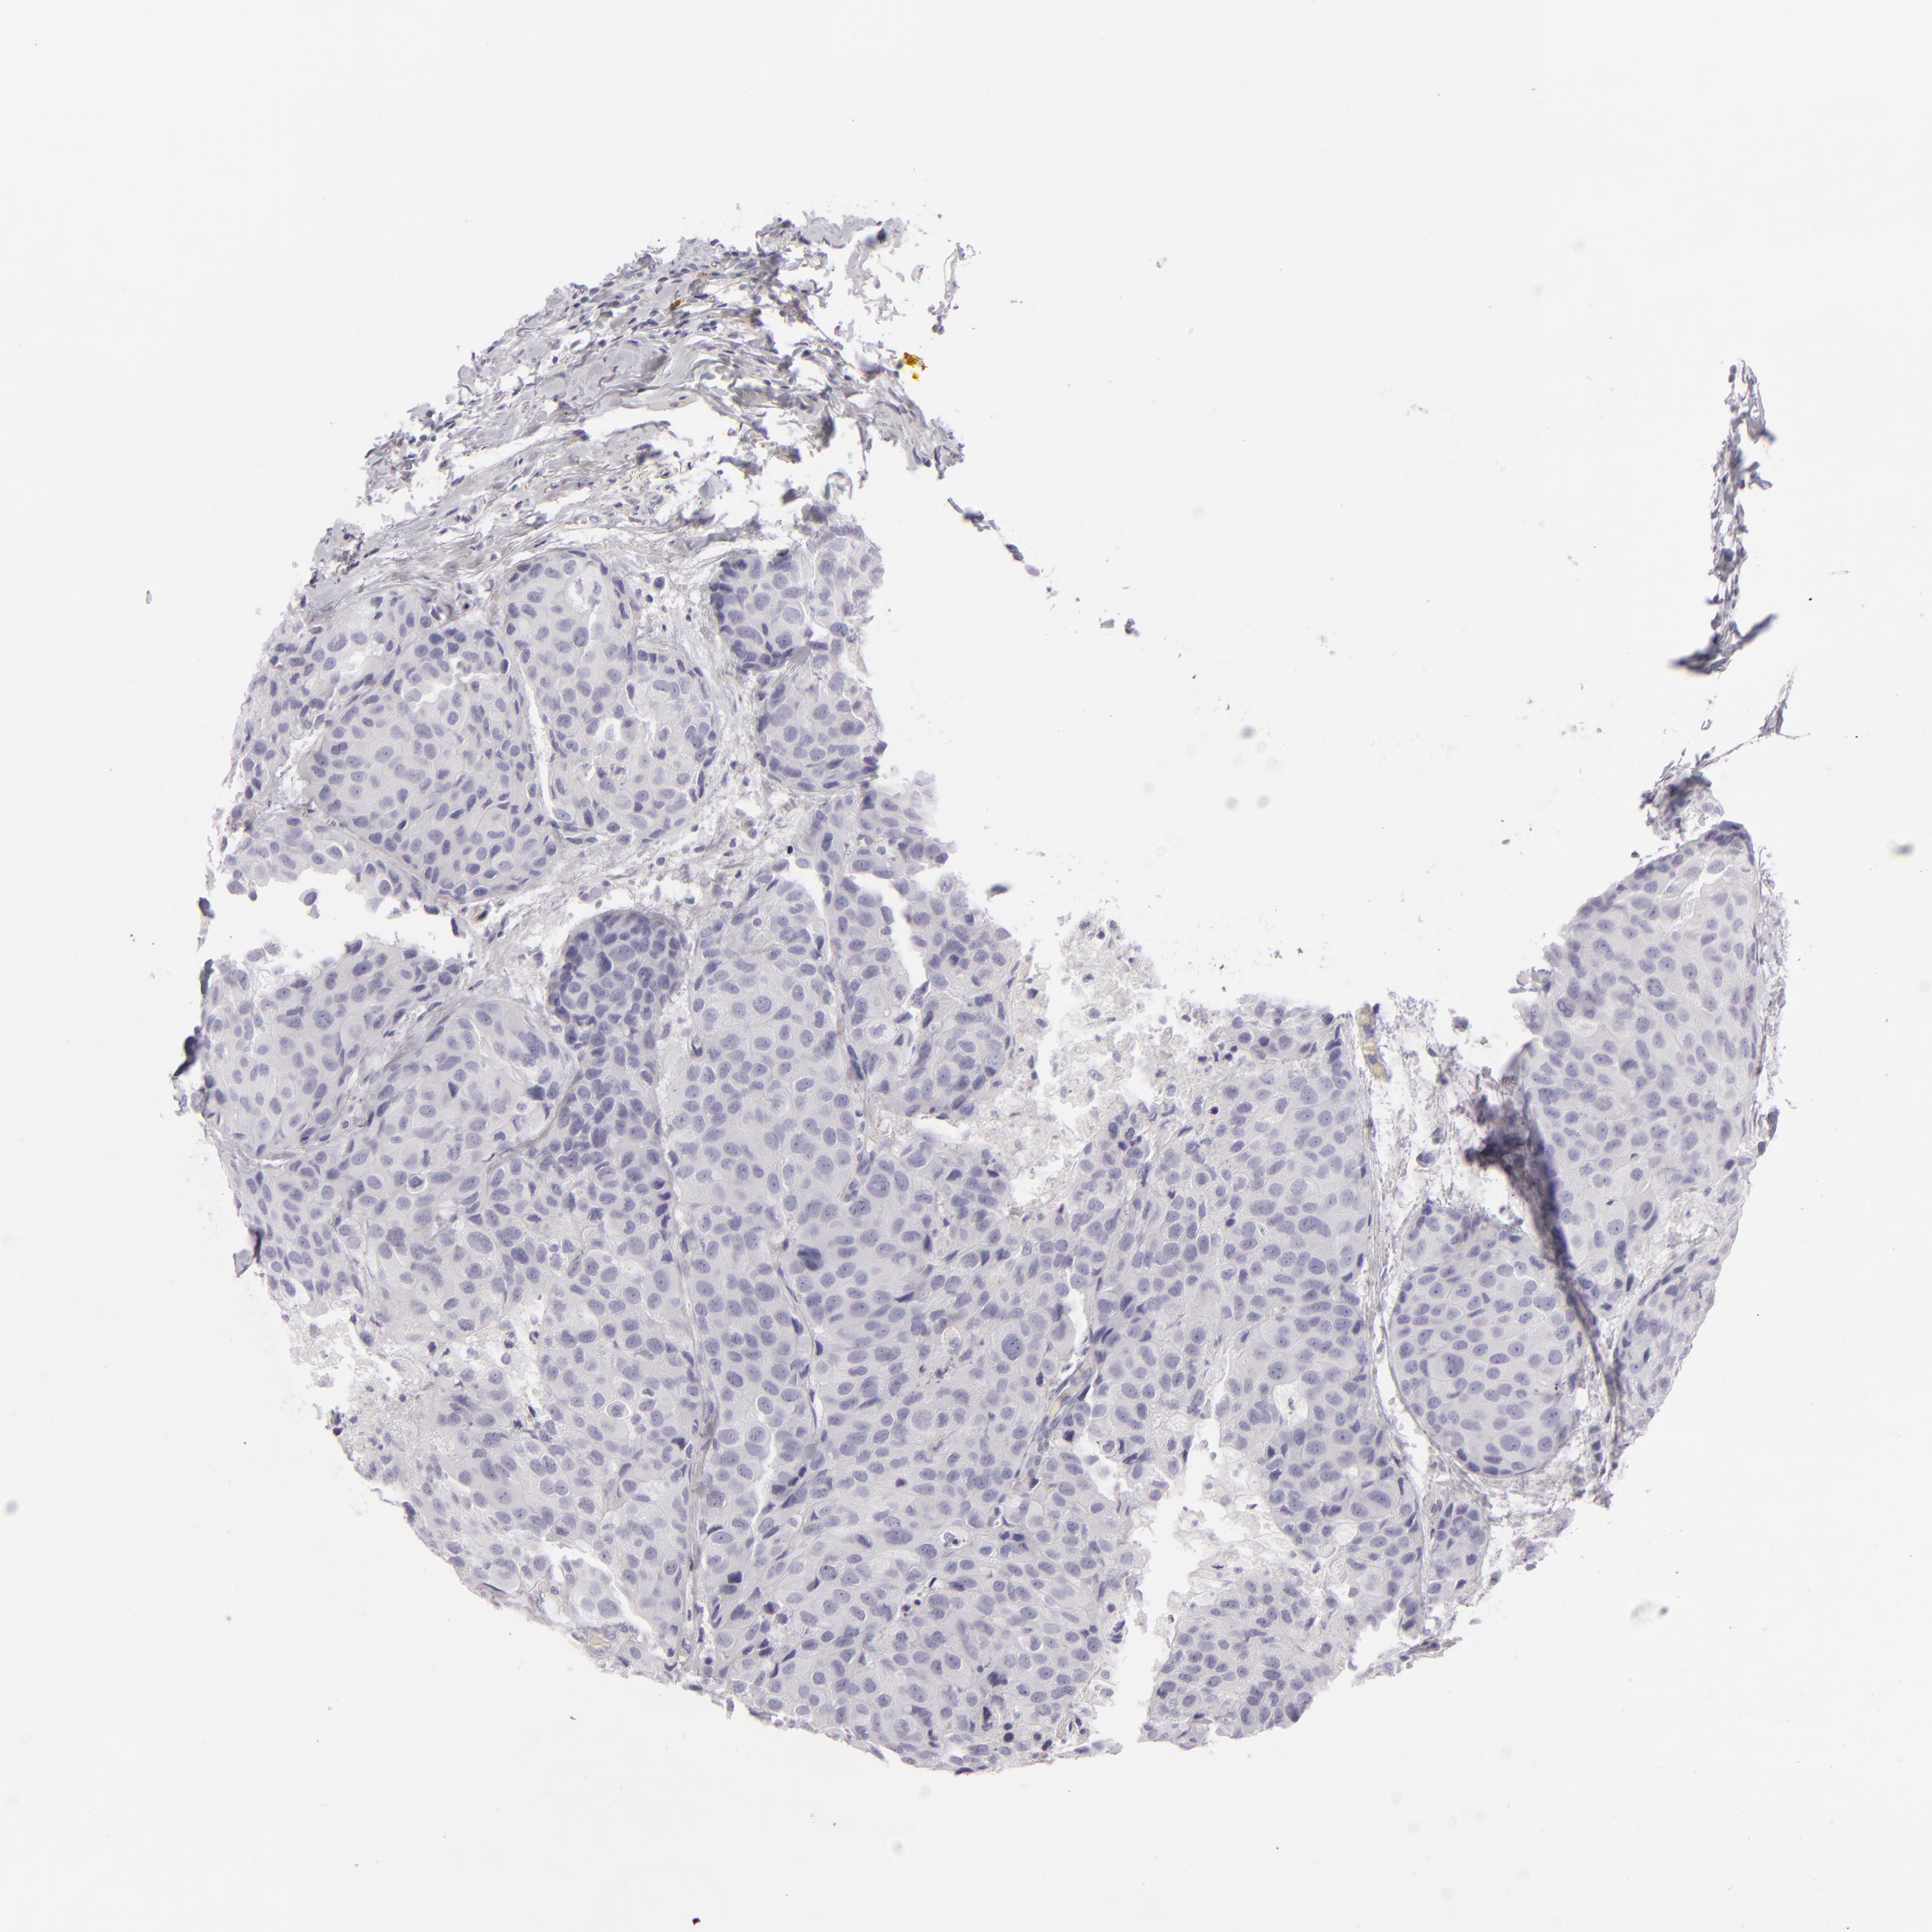

CDX2

• CDX2

CANCER BREAST CANCER Show tissue menu

Breast cancer

Human cancer